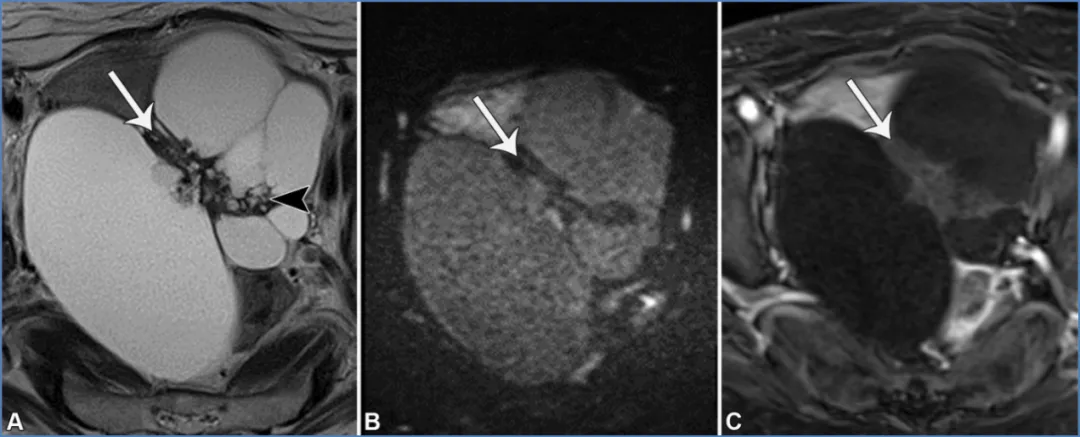

对于30岁以下、单侧卵巢实性病变且乳酸脱氢酶升高的女性,最可能的诊断是无性细胞瘤(36,62)。无性细胞瘤是一种恶性生殖细胞肿瘤,为睾丸精原细胞瘤的卵巢对应肿瘤,表现为单侧非低信号T2/非低信号DWI实性病变,由T2低信号、强化明显的纤维血管间隔分隔成小叶(图28)(62)。相反,在30岁以下女性中,甲胎蛋白升高基本可诊断为卵黄囊瘤,而β-人绒毛膜促性腺激素升高基本可诊断为绒毛膜癌(36,62)。

图28. 一位20岁女性患者的左侧卵巢无性细胞瘤,其乳酸脱氢酶(LDH)水平升高。轴位T2加权像(A)、高b值扩散加权像(B)、表观扩散系数(ADC)图(C)及对比增强脂肪抑制T1加权像(D)显示,卵巢存在一个T2信号中等的实性病灶,伴有弥散受限(B图呈高信号,C图呈低信号)且有强化。该病灶被纤维血管间隔分隔成小叶,这些间隔在T2加权像上呈特征性的中低信号(A图箭头),在对比增强像上呈明显强化(D图箭头)。